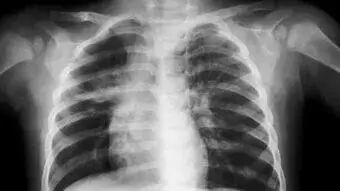

根据英国移民局规定,从2013年12月31日开始,如果申请者是中国居民并打算申请赴英停留超过6个月, 那么必须在指定的检验机构进行肺结核检测并确保未感染肺结核,方可申请签证。

肺结核检测是做胸透检测,需要脱去上衣。所以如果有需要预约女性医生的话,可在预约时强调说明一下。

千万不要患感冒或者咳嗽时去做检查,因为这样肺部容易检查出阴影。专家会让大家去预约做痰检,痰检需要两个月的时间出结果,其次花费非常的高。真的非常的耽误时间,甚至可能错过交签证最后的deadline! 一定要在身体健康的情况下做肺结核检查!

一般来说,如体检者无需进行进一步结核筛查,可在1个工作日内领取结核筛查证书,该证明在6个月内有效;如果体检中发现活动性或陈旧性肺结核表现,则需要做进一步痰液检查。

患有急性支气管炎、肺炎等肺部疾病者,如果时间允许请推迟体检时间;